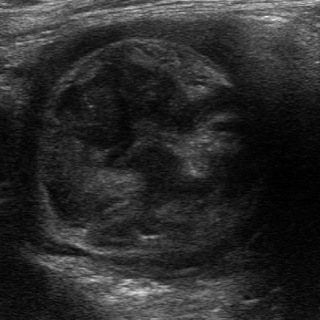

Image echographique

d'une invagination ileo-colique sur adenocarcinoma

du colon droit . Coupe tranverse . |